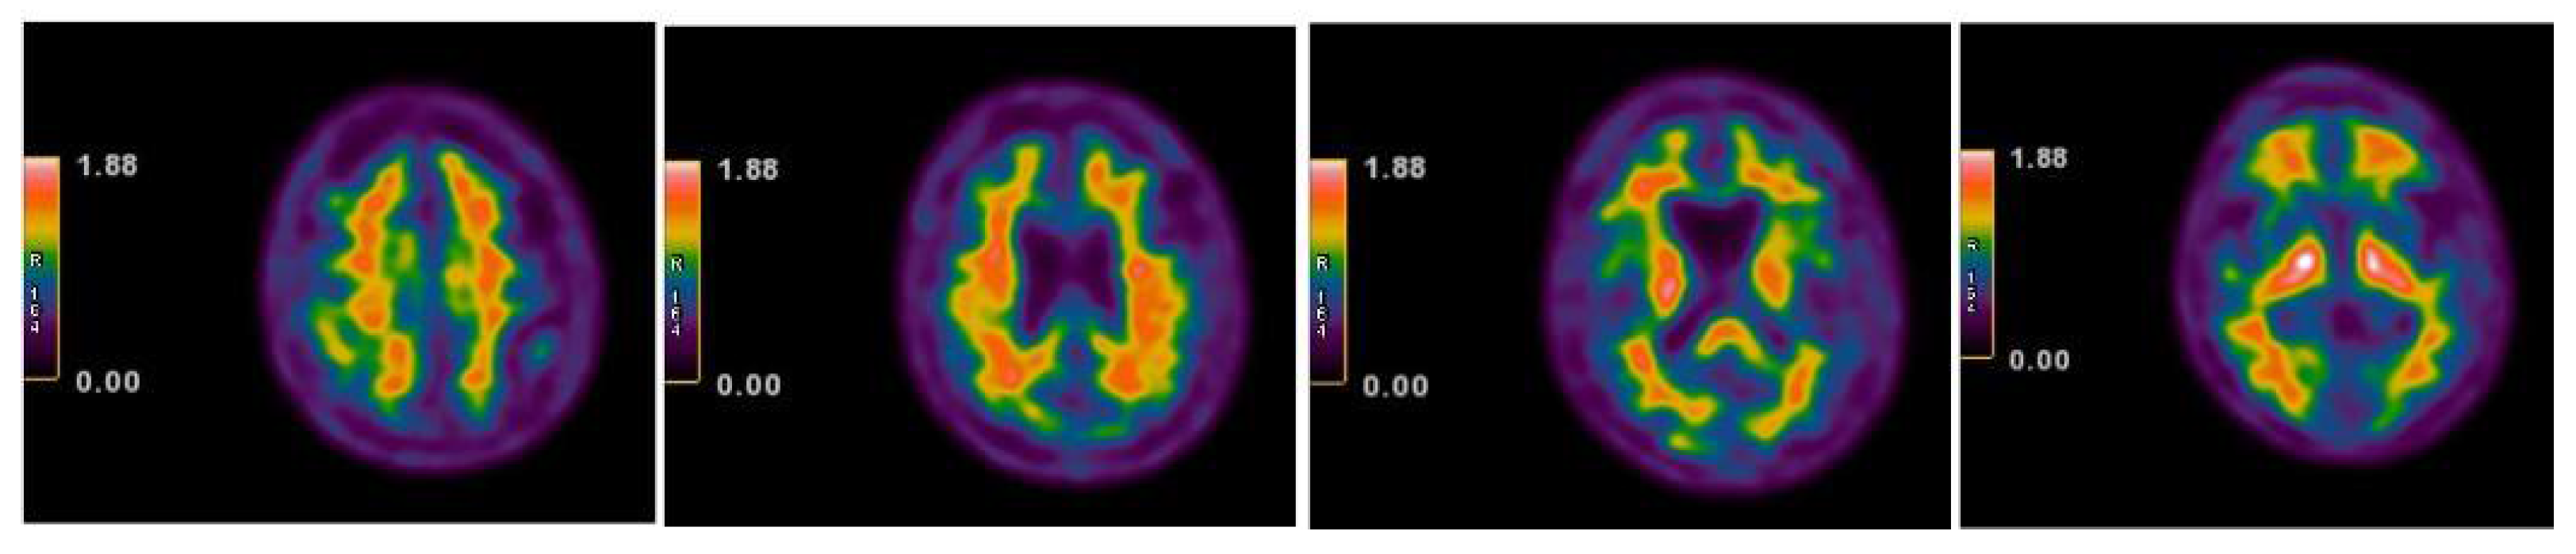

| 2013 | FDG-PET | Hypometabolism in the right and left premotor cortex |

| 2015 | Neurological assessment FDG-PET | Mild isolated motor speech disorder hypometabolism; more extensive involving left temporal gyrus, frontal gyrus bilaterally, cingulate, caudate, and thalamus bilaterally |